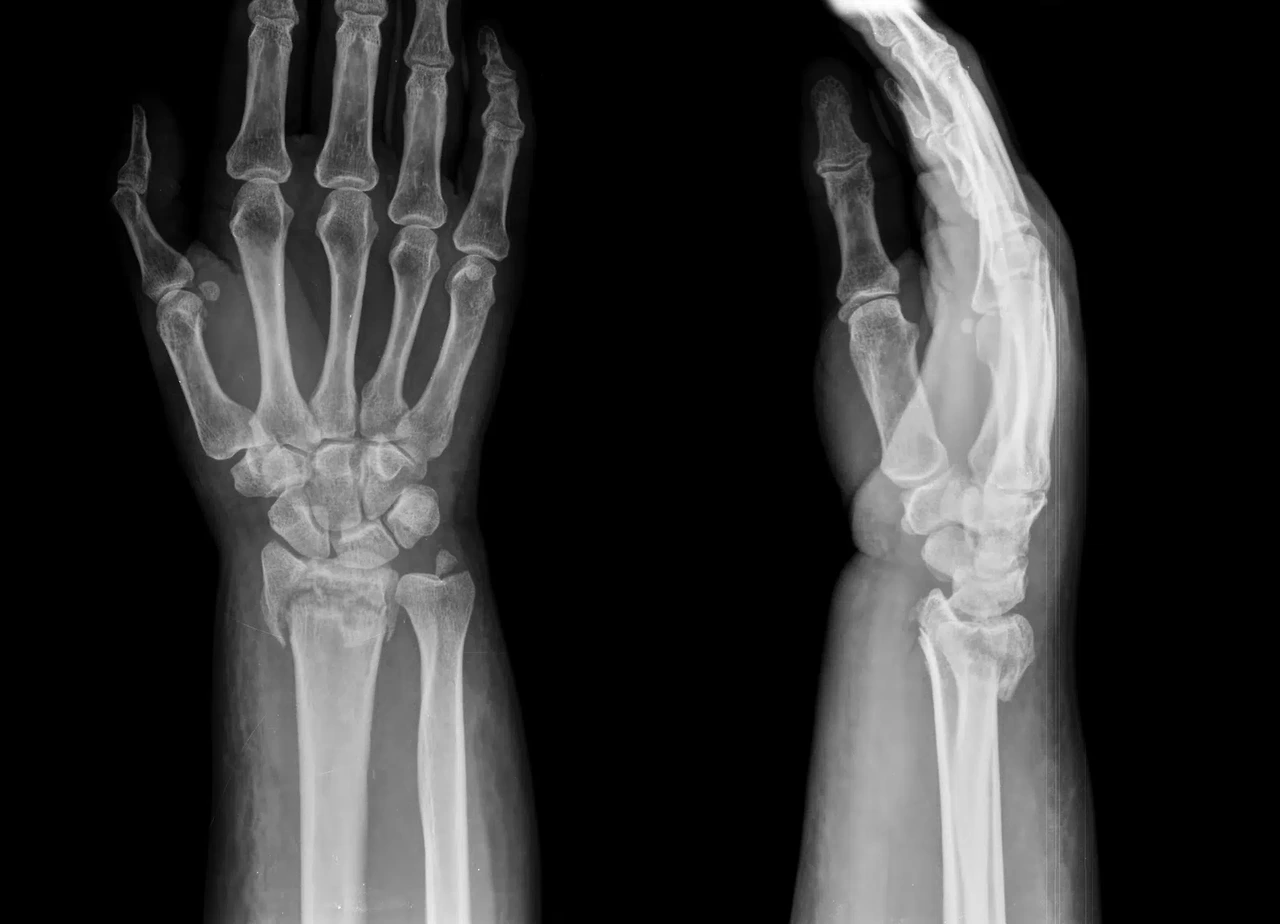

- 손목 골절

넘어지며 손을 짚는 과정에서 발생하며, 수술과 장기간 고정이 필요해 일상생활에 큰 불편을 줍니다.